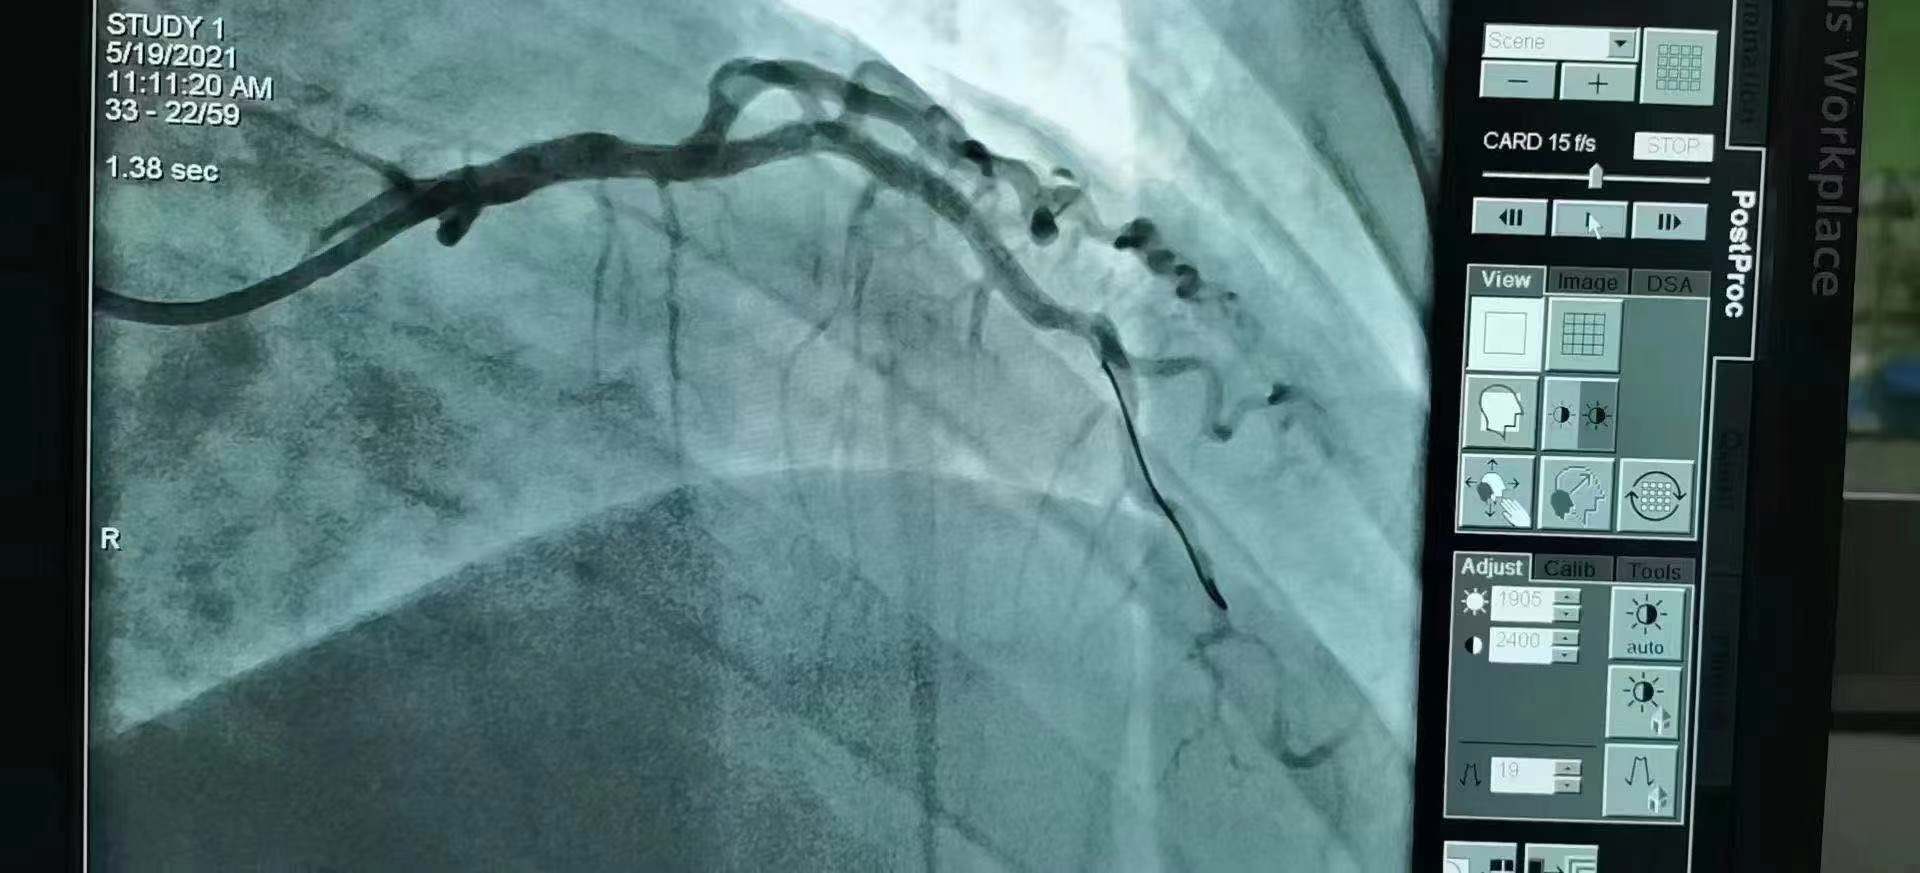

青島市第三人民醫(yī)院 李曉主任團隊成功為患者植入Xinsorb生物可吸收支架!

祝賀 青島市第三人民醫(yī)院  李曉主任團隊成功為患者植入Xinsorb生物可吸收支架!